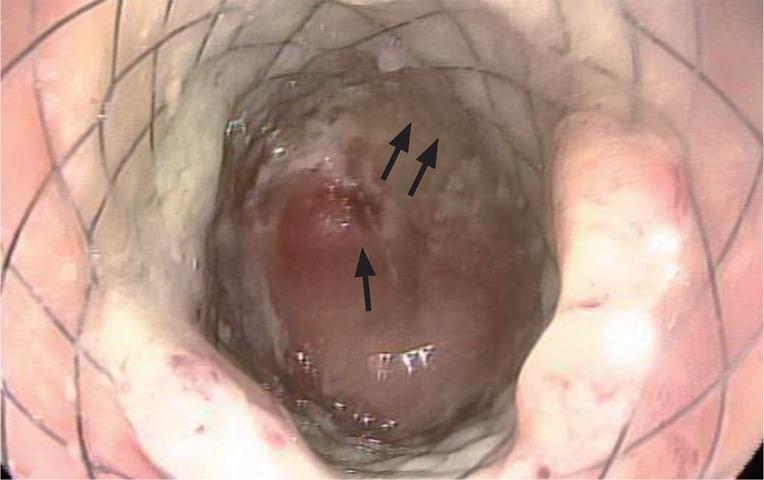

Successful management of colonic perforation with a covered metal stent.

Self-expandable stents are widely available for the treatment of perforation of the gastrointestinal tract. Because of the risk of migration, there has been no report of the use of self-expandable stents for the treatment of perforation of the colon or rectum. This is a report of successful treatment of iatrogenic colonic perforation during balloon dilatation of anastomotic stricture with a fully covered stent. Fully covered, self-expandable metallic stents can be considered useful tools for management of this condition.